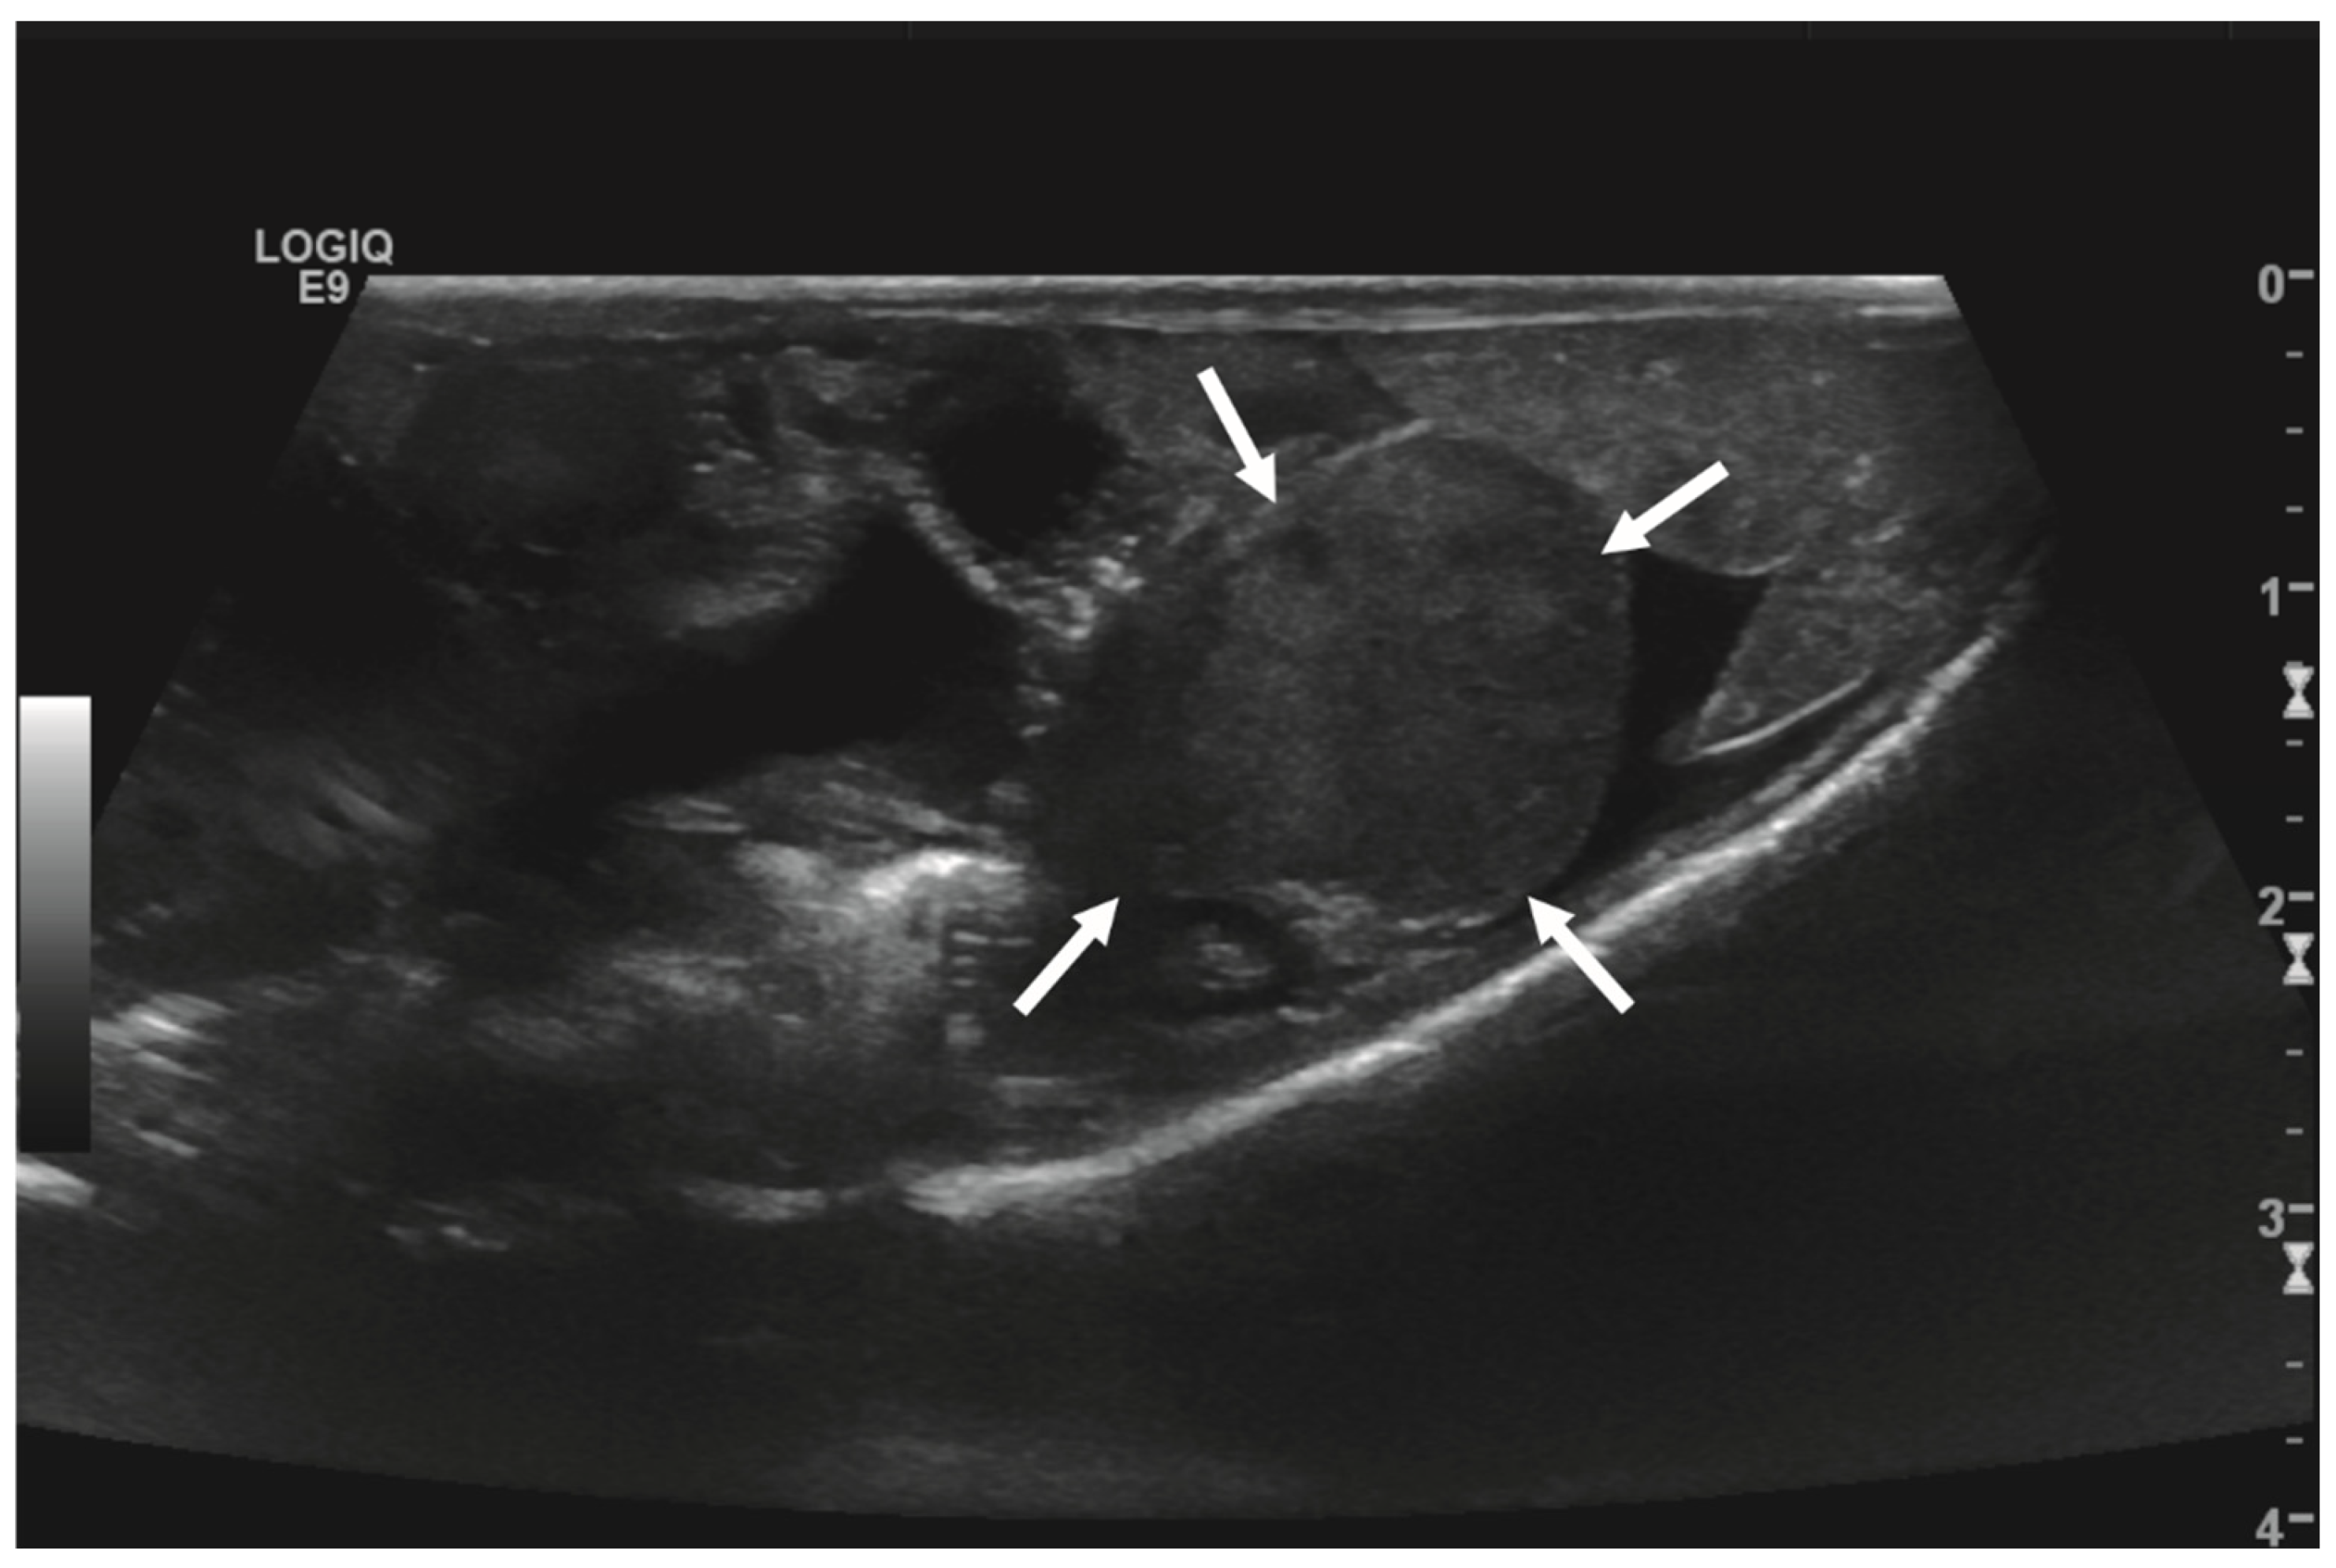

Initial diagnostic methods included parasitological fecal examination, radiography, and ultrasonography. The animal owner declined a blood examination due to financial restrictions. Microscopic fecal examination at 100× magnification revealed a high infestation of oxyurids (>20 eggs per field of view) and a low-grade flagellate infestation. Under manual restraint, dorsoventral and horizontal beam lateral radiographic projections were performed (Figure 1; digital X-ray; detector system: Fujifilm Console Advance DR-ID 300 CL, Fujifilm Europe GmbH, Düsseldorf, Germany; tube system: Gierth X-ray International GmbH, Riesa, Germany; film focus distance FFD 60 cm, 50 kV, 5 mAs). The lateral radiograph was insufficient for any evaluation due to a technical issue. On the dorsoventral view, the medial right coelom was filled with soft-tissue material and hypodense areas (moderately filled gastrointestinal tract and gastrointestinal gas). Mineral opacities were visible in the left coelom, indicating deposits of foreign material (sand or similar anorganic substrate) in the large intestine. Both lung fields were visible on the dorsoventral radiograph, though superimpositions with the gastrointestinal tract did not allow a clear evaluation of the entire lung field size. No distinct intracoelomic lesion was determinable upon radiography. Ultrasonographic examination under manual restraint and in dorsal recumbency (Micro curved array transducer, 5–9 MHz; Vivid 7 Dimension; GE Healthcare GmbH, Solingen, Germany) with transverse and longitudinal views from the ventral coupling site showed an approximately 2 × 1.5 cm round-shaped, intracoelomic mass located in the middle third of the medial right coelom. The structure was surrounded by intestinal and fat body tissue (Figure 2). However, the mass showed good vascularization, and demarcation to surrounding tissue was clearly feasible (Figure 3). No other abnormalities of coelomic organs were visualized during the ultrasound examination.

Figure 3. Transverse ultrasonographic image of the medial right coelom in a bearded dragon acquired with a 5 to 9 MHz micro curved array transducer and Color Doppler evaluation (penetration depth 2 cm; frequency 15 MHz). Note the distinct vascularization of the round-shaped intracoelomic mass (arrows). Additionally, gastrointestinal tract (medial, here: to the left of the mass) and fat body (lateral, here: to the right of the mass) are visible and closely related to the mass.